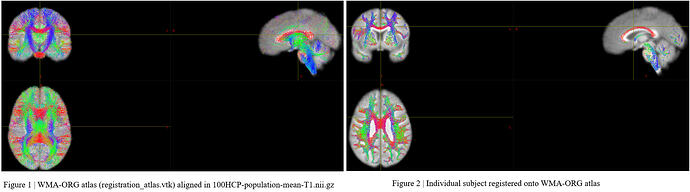

Recently, I am focusing on using big data like ADNI to explore white matter fiber tractography in different groups. I used Mrtrix3 (iFOD2) to generate the whole brain fiber tractography (whole_tract.tck). After that, I used ‘tckconvert‘ command to convert the ‘whole_tract.tck‘ to ‘whole_tract.vtk‘. Then I used the WMA package ( whitematteranalysis | White matter tractography clustering and more… ) to register ‘whole_tract.vtk‘ onto ORG-atlas (registration_atlas.vtk). I have tried to used both “rigid-affine” and “affine + nonrigid“ registration methods, but the results shown in Figure 2 looks like the commissural fibers not following the pattern of corpus callosum. I am not sure what’s wrong with it. My codes are as follows: